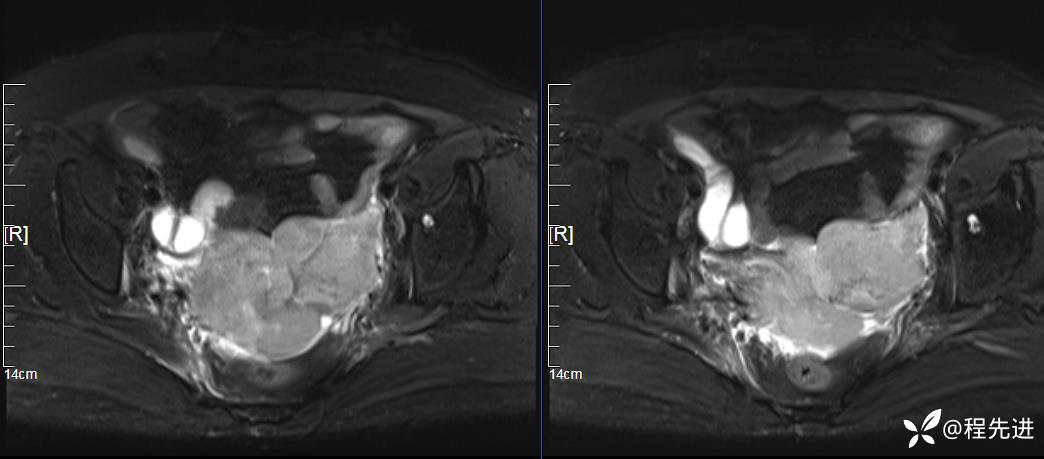

DWI、ADC:

患者性别:女

患者年龄:76岁

简要病史:下腹痛伴发热半月余

实验室检查:肿瘤指标均正常